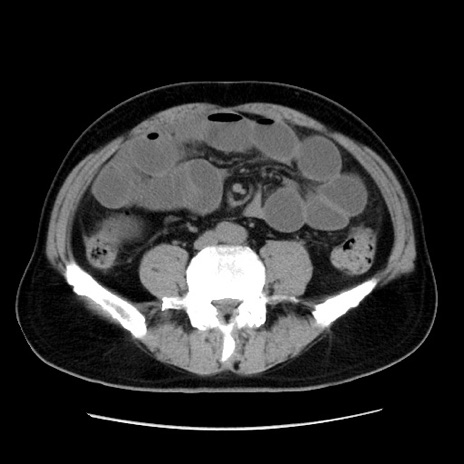

症例16(横断像)

【症例】 70歳代男性

【主訴】 腹痛、嘔吐

【現病歴】 約1ヶ月前より間欠的に腹痛と嘔吐あり、当院消化器内科を受診したところCTで多発する肝臓のLDAを指摘され、精査中であった。以降は消化器症状は安定していたが、2日前より嘔気と腹痛があり、同日より排便・排ガスが消失した。改善認めず、 本日、救急外来を受診した。

【既往歴】 大腸ポリープ切除後。

【身体所見】意識清明・会話良好、BT 36.3℃、BP 127/80mmHg、 P 80bpm、腹部:膨満あり、平坦・軟、上腹部正中および下腹部正中に圧痛あり、反跳痛なし、筋性防御なし。

【データ】WBC 7200、CRP 0.77